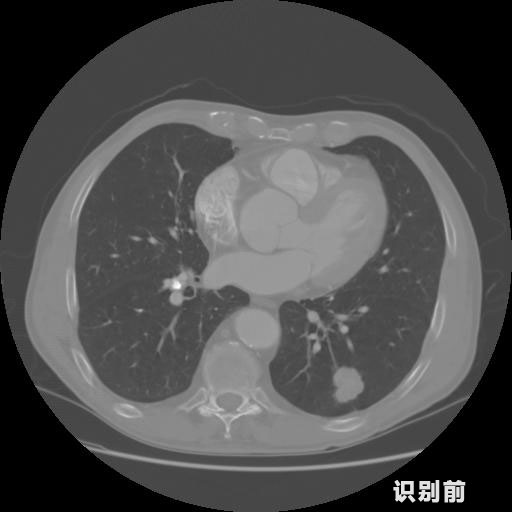

英特健康AI深度學習醫療圖像識別系統案例_胸部CT

1.發現肺結節的可能性為95.56%---位于框指數位置:[331.70554 366.13406 365.21707 403.96234]